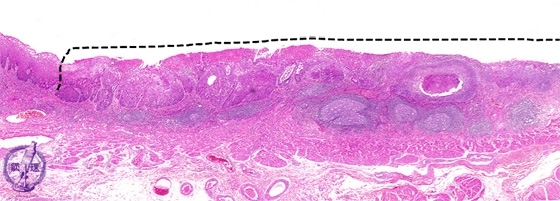

- ★(3)Esophageal carcinoma (squamous cell carcinoma)

Microscopic view (H&E stain, low power): Esophageal squamous cell carcinoma (early carcinoma). An example of intramuoscal carcinoma (dotted line).

Click the image to see the enlarged image.